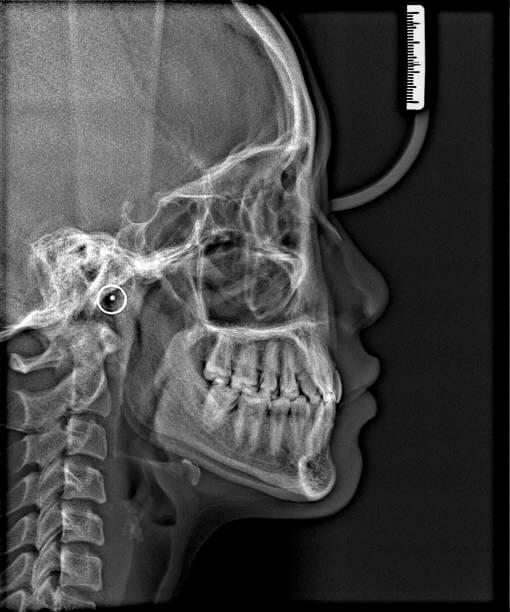

| 정밀검사 | 두부방사선 사진(Cephalo) 등을 통해 성장 방향 확인 |